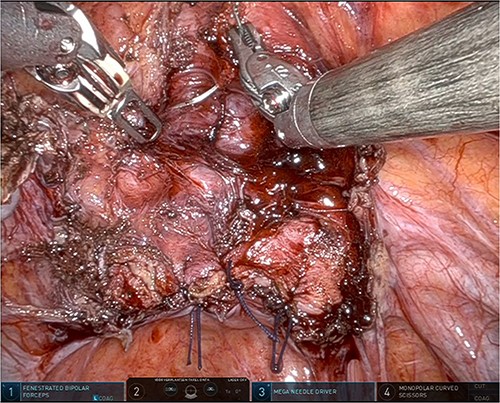

The patient was planned for a robotic resection of the endometriosis nodule and hysterectomy by an experienced robotic gynecological surgeon. The patient was placed on a PinkPad (Kebomed Europe AG) in a lithotomy position. Cystoscopy was performed with placement of ureteral stents. Double-J stents were guided up to the kidneys. Instillation of 200 ml physiologic water with 2 cc of ICG (1.9 mg/cc) in an empty bladder, with subsequent clamping of the urinary catheter (Fig. 3). The da Vinci Xi robot platform (Intuitive Surgical Inc.) was used. Instruments used were: bipolar fenestrated forceps, unipolar scissor, Cadière forceps, and Vessel Sealer Extend. Circumferential incision, dissection and detachment of the endometriotic nodule from the posterior bladder wall was performed under guidance of NIR imaging and ICG, whilst the endometriosis nodule remained stuck on the uterine isthmus (Fig. 4; Supplementary Video). During the dissection, perforation of the bladder mucosa could be avoided, with transparency of the bladder mucosa by ICG. During the hysterectomy part, the bladder catheter was unclamped. The posterior bladder wall was repaired longitudinally. The muscular layers and serosa of the bladder were sutured with Monocryl 3/0 in a two-layer closure (Fig. 5). The bladder was filled with 200 cc of physiologic water with ICG, no bladder leakage nor clear transparency by ICG of the posterior bladder wall was seen. The total operative time was 120 min. The total blood loss was 25 mL. There were no perioperative complications. The length of the hospitalization was 48 hrs. Oxybutynin was given to prevent bladder spasms from the urinary catheter and/or stents. The Foley catheter was removed after 9 days, and the ureteral stents removed after 10 days. At the 2-week outpatient visit the patient was satisfied, and didn’t experience any pain nor urinary voiding problems.

Robotic dissection of the endometriosis nodule between the isthmus of the uterus and bladder; lateral dissection with bilateral transparency of ICG of the thin posterior bladder wall.